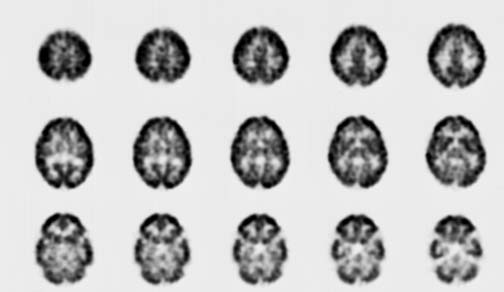

CaseHE02

- Age/Sex: 3 M

- Chief Complaint: けいれん発作重積状態

- Images:

- Tc-99m ECD Aug/27

- Tc-99m ECD Aug/31